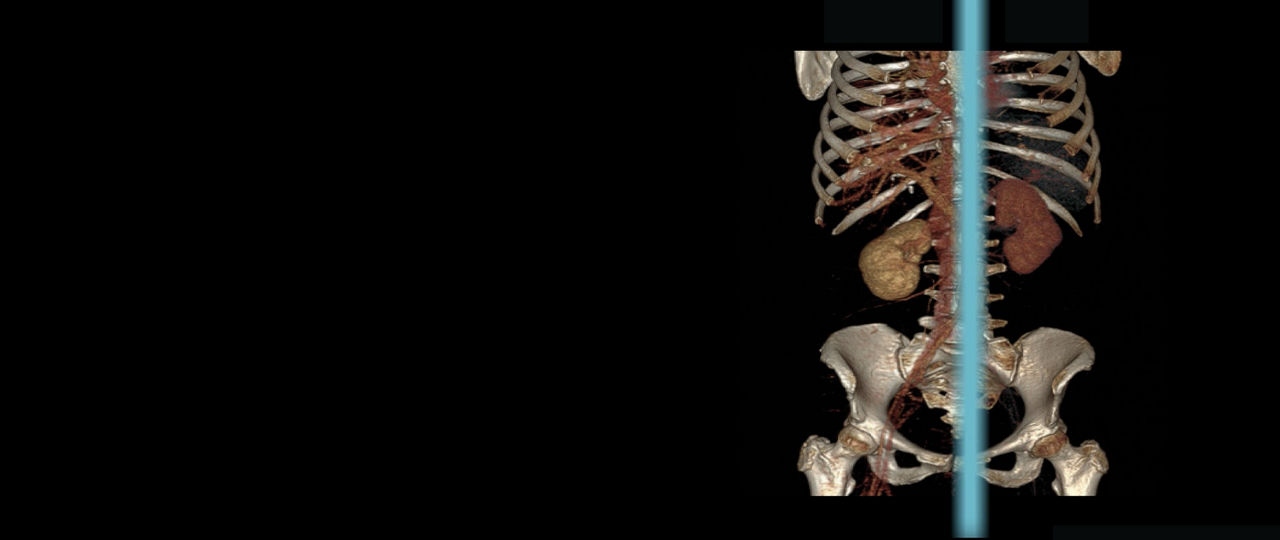

Revolution™ CT with Apex Edition upgrade

Explore our versatile CT platform with built-in scalability and upgradability. Choose the cost-effective hardware and powerful software configuration you need now and easily integrate advanced capabilities in the future